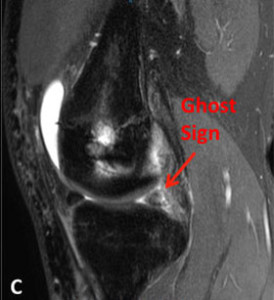

Meniscal Root Tear Meniscal root tears can be seen on coronal, axial and sagittal MRI views. On the sagittal view, as seen in Figure C, there is a “ghost sign” which is indicative of meniscal root tear. A normal, healthy meniscus should look like a dark black triangle; however, as this figure shows the meniscus is much lighter or “ghosted” representing the root tear.